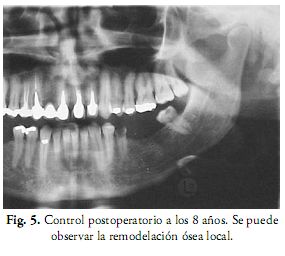

El diagnóstico histopatológico establece la presencia de tejido óseo compacto con osteocitos diferenciados y de conjuntivo interóseo constituido por fibroblastos (Fig. 4). El diagnóstico definitivo fue de osteoma periférico. La asimetría facial fue corregida y no hubo recidiva en el seguimiento de ocho años (Fig. 5).